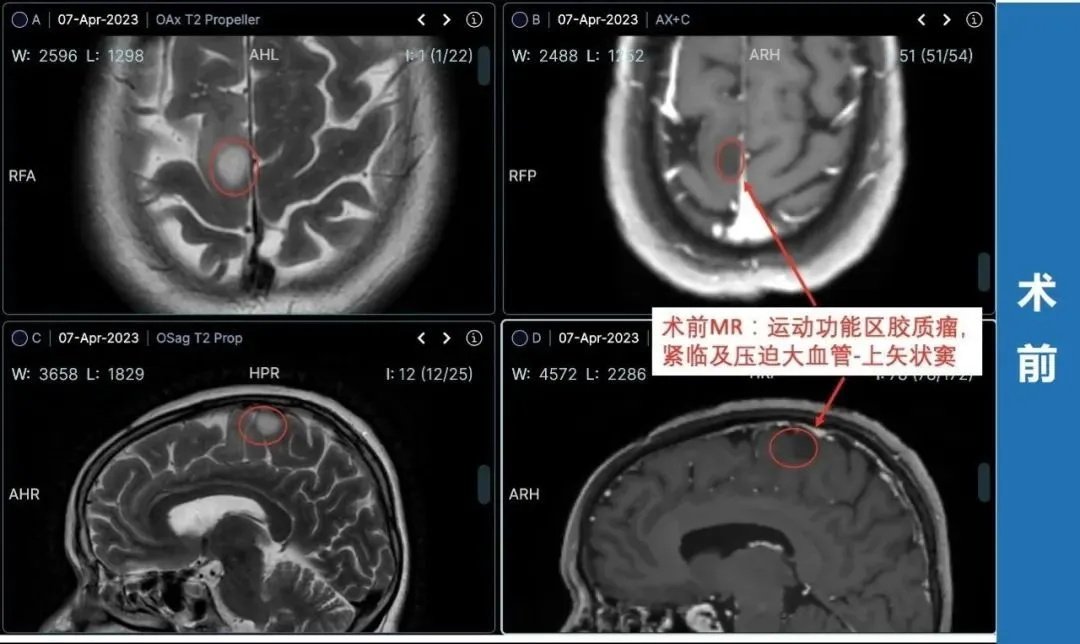

▼治疗过程:4月2日,罗女士和家人一致决定找巴教授手术,这时距离罗女士咨询巴教授仅过去了2天。

4月,苏州独墅湖医院神经外科,INC德国巴特朗菲教授为额叶胶质瘤合并癫痫发作患者——66岁的罗女士顺利行肿瘤切除,在术中导航、术中核磁、术中神经电生理监测下,肿瘤取出的同时也保护了大脑正常功能。

术后情况:术后4周时,罗女士术后因水肿引起的暂时性左侧肢体无力情况已完全恢复,肢体活动正常,准备出院回家好好享受生活。罗女士家人交流了罗女士的康复锻炼视频,罗女士恢复良好,行走自如。